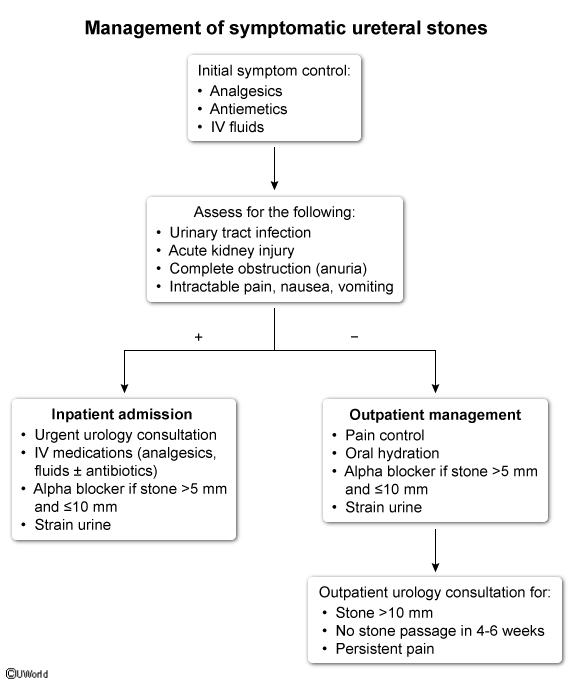

what medication can be used to help pass a kidney stone?

tamulosin (a1 antagonist)